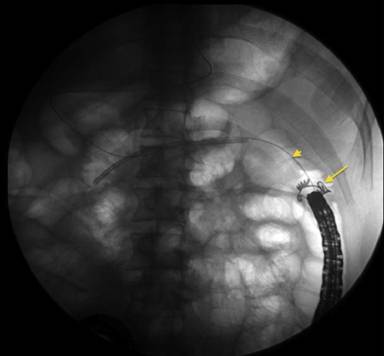

Because pancreatic sphincterotomy and pancreatic duct stenting was unsuccessful, we attempted endoscopic clip closure of the fistula. A 0.025” angled guidewire was advanced into the pancreatic duct, across the fistula, and into the colon. The duodenoscope was removed, leaving the wire in place. An over-the-scope clip (Ovesco, Campbell, CA, USA) was attached to the end of a colonoscope which was advanced to the splenic flexure (Figure 2). The fistula was identified by the wire protruding from it (Figure 3). The cap was positioned en face to the fistula and the wire slowly withdrawn. Using a grasper, tissue was pulled into the cap and suction applied. The clip was deployed and in good position (Figure 4).

Figure 2. A fluoroscopic view of the over-the-scope clip (arrow) at the level of the splenic flexure and the angled guidewire (arrowhead) advanced across the fistula and into the colon. |